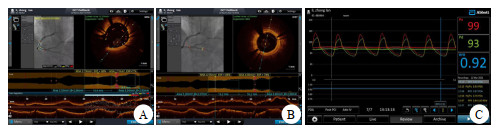

LAD一周后(12月11日)行旋磨:消毒,铺巾,穿刺右锁骨下静脉,置入临时心脏起搏电极(图 4A),单腔起搏方式60次/min起搏保驾。LAD狭窄与环状钙化处选1.25 mm旋磨头反复3次旋磨。OCT检查示,钙化结节消失,球囊反复扩张,狭窄明显好转,选2.75 mm×33.00 mm支架植入LAD病变处(图 4B),OCT检查有部分支架贴壁不良现象,再用后扩球囊反复扩张,再次OCT检查支架无膨胀不全及贴壁不良(图 4C),冠脉造影未见残余狭窄,FFR 0.94。11 d后康复出院,心肌酶趋势图显示恢复良好(图 2)。

| A为LAD 80%狭窄,FFR 0.76;B为旋磨后支架植入FFR 0.94;C为旋磨及支架植入后OCT检查无贴壁不良及膨胀 图 4 病例1的术后冠脉造影及OCT检查结果 |